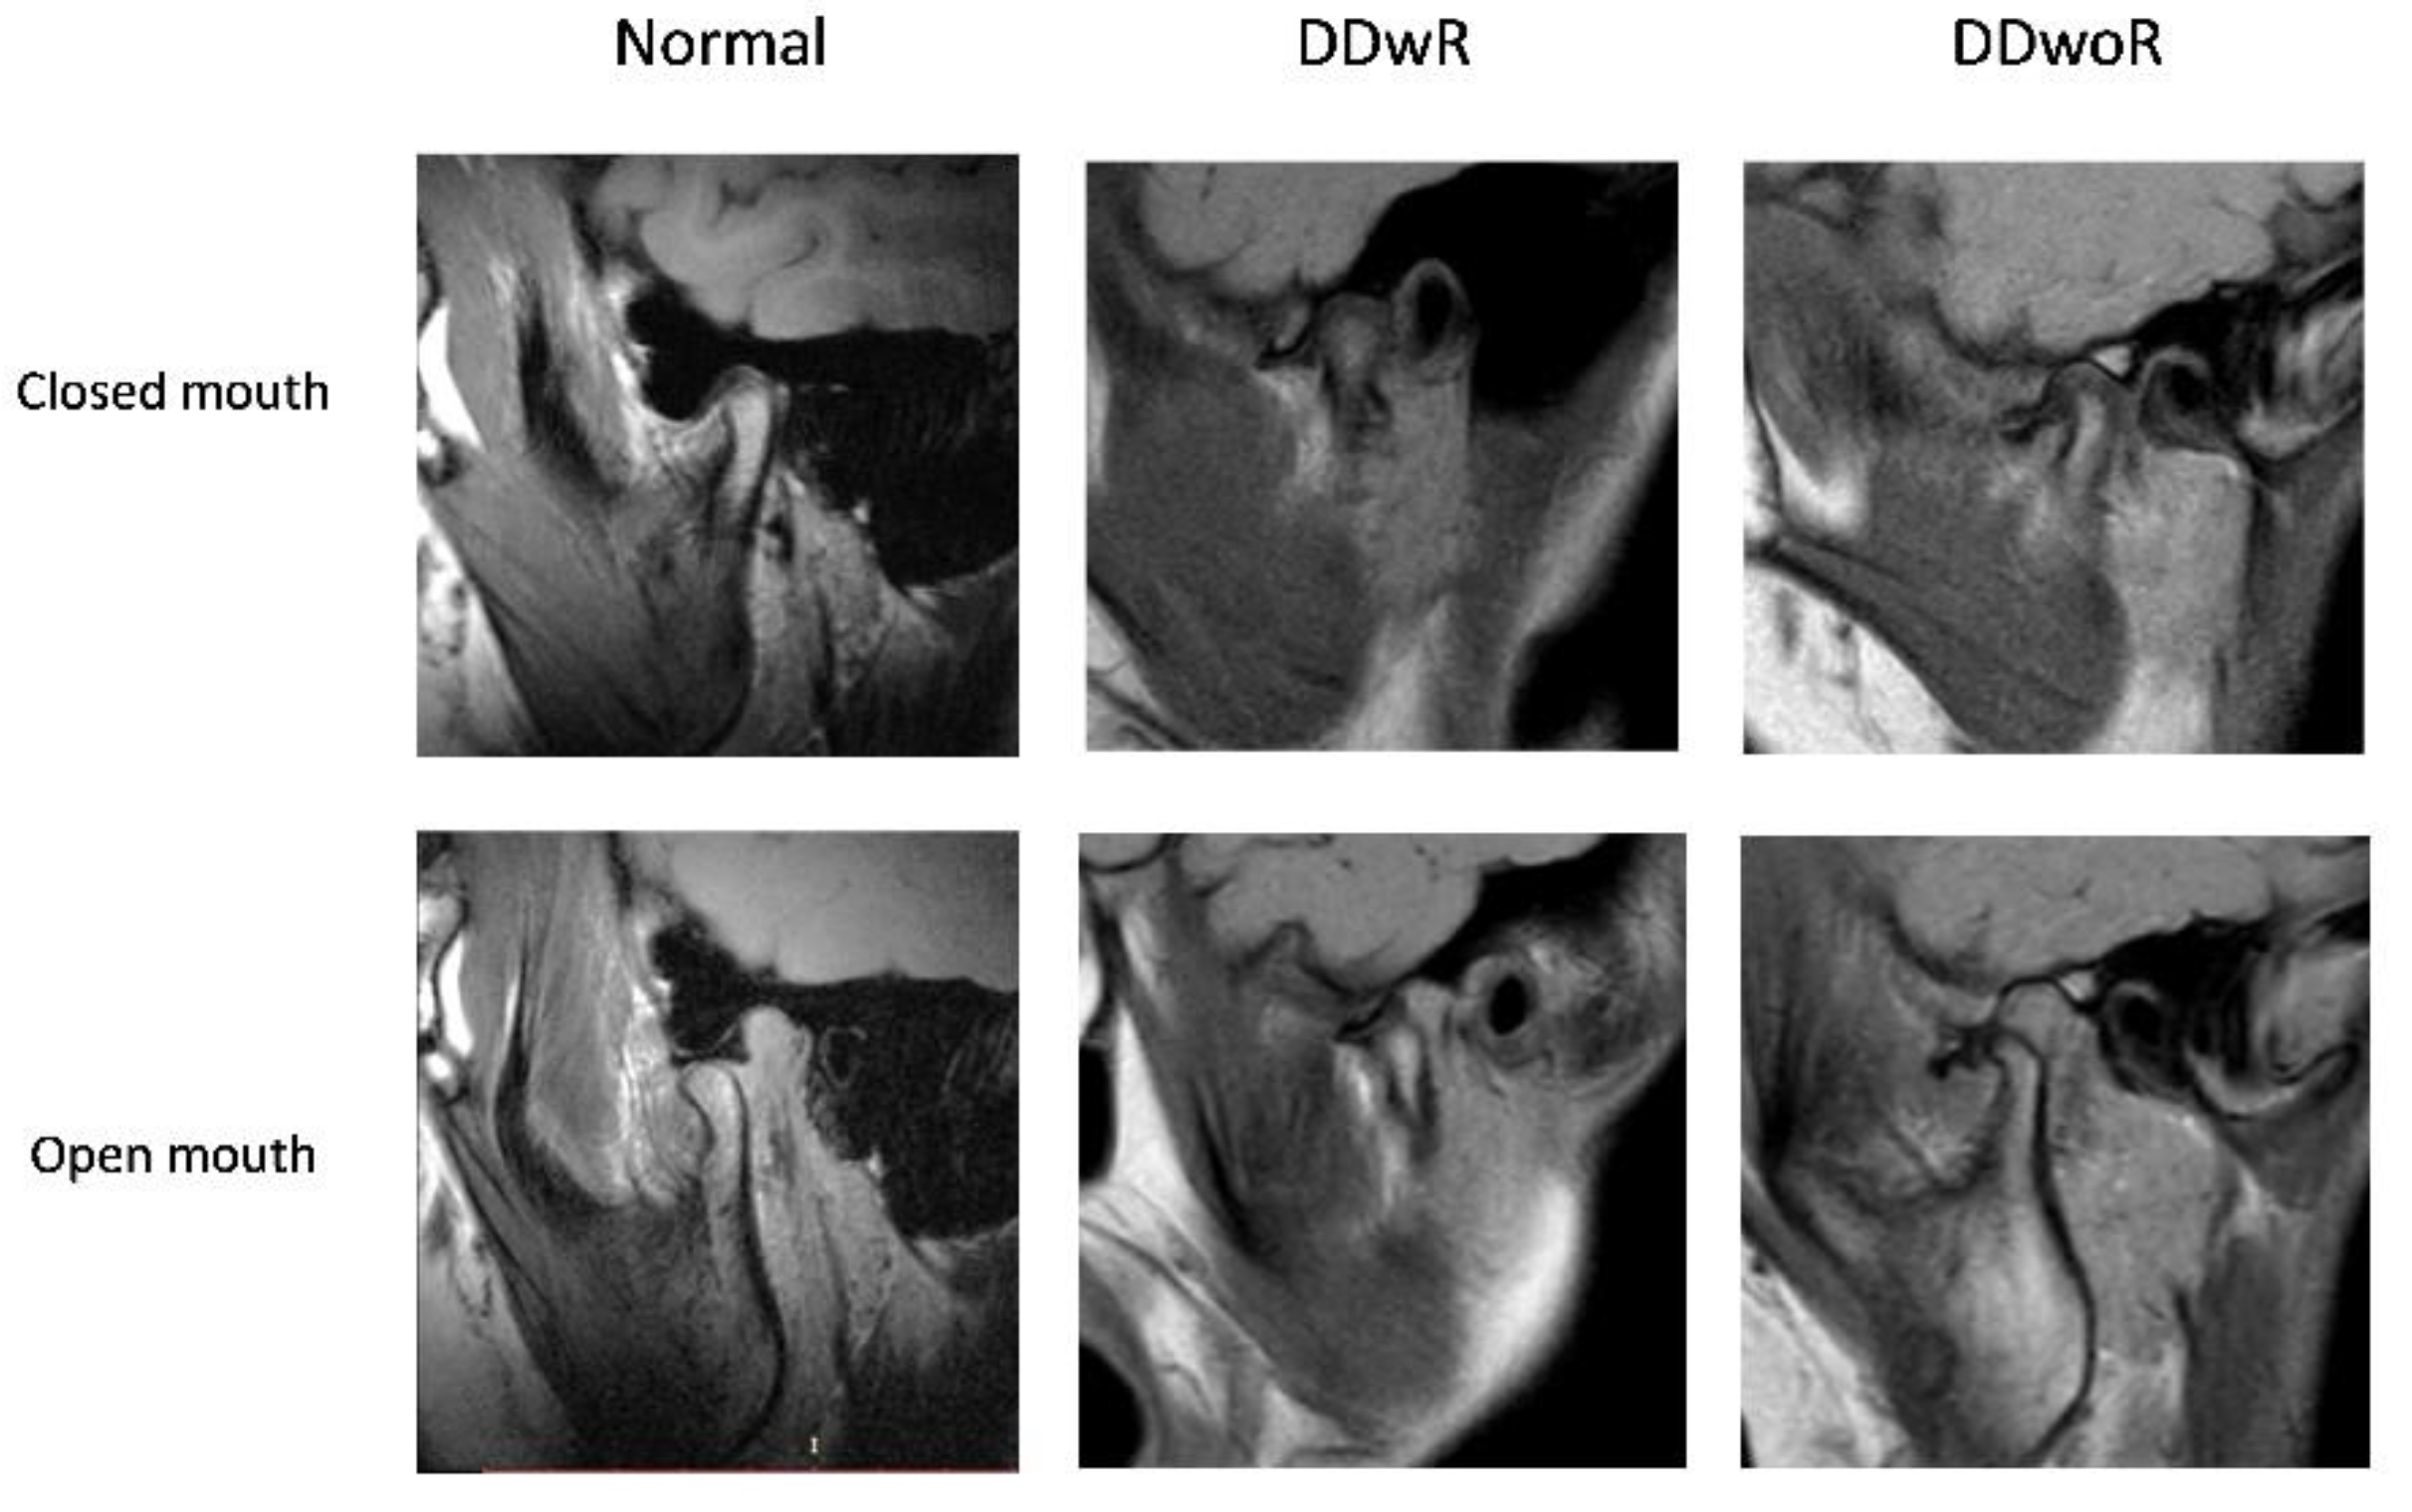

Normal disc position (N), when in closed-mouth position, the posterior band of the disc was positioned above the apex of the condylar head (in a 12 o'clock position), while in an open-mouth position the intermediate zone of the disc was interposed between the condyle and the articular eminence; in coronal projection, the disc was located over the head of the condyle; in open-mouth, the disc remained interposed between the condyle and the articular surface of the articular eminence.

Disc Displacement with reduction (DDwR), when in sagittal projection, in a closed-mouth position, the posterior band of the disc was anteriorly displaced relative to the head of the condyle and in coronal projection could appear in a normal position over the head of the condyle and/or displaced medially or laterally. However, the articular disc was reduced on mouth opening.

Disc displacement without reduction (DDwoR), when in sagittal and/or coronal planes, in both closed-mouth position and open-mouth position, the posterior band of the disc was displaced relative to the head of the condyle and in an open-mouth position, the correct relationship of the condyle-disc complex was not restored. (Figure 1)

Figure 1. Disc position based on open-mouth and closed-mouth. DDwR: disc displacement with reduction; DDwoR: disc displacement without reduction.